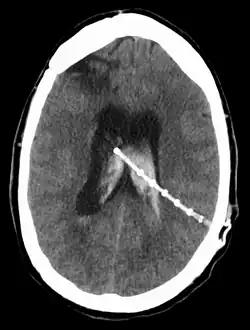

Een ventrikeldrain is een drain of shunt (kunststof afvoerbuisje) in de ventrikels van de hersenen en wordt door een neurochirurg geplaatst in de steriele omgeving van een operatiezaal. De functie van de ventrikeldrain is tweeledig. Enerzijds kan men via deze drain de druk van het hersenvocht meten. Anderzijds kan men, indien nodig, bij overdruk ventrikelvocht draineren (afvoeren) in een recipiënt (zakje, bakje, holte) om zo de hersenen meer ruimte te geven en de druk van het hersenvocht op de hersenen te verminderen. De tip van de ventrikeldrain bevindt zich in de ventrikels, in het midden van de hersenen. Normale menselijke hersenen bevatten vier ventrikels, meestal bevindt een ventrikeldrain zich in de derde en grootste ventrikel.

Een toepassing van een ventrikeldrain is de VPD (ventriculoperitoneale drain(age), VP-drain) bij een waterhoofd (hydrocefalus) waarbij een kunststof buisje (drain of shunt) met ventiel van een hersenventrikel naar de buikholte wordt aangelegd voor permanent gebruik zodat overtollig hersenvocht (liquor) wordt afgevoerd en vergrote ventrikels tot normale afmetingen kunnen slinken. Deze operatie (neurochirurgie) duurt ongeveer 2 uur, daarna is nog minstens één ligdag in het ziekenhuis nodig. Dit type drain wordt na de operatie niet meer ontsmet maar moet in tegendeel na een herstelperiode van bijvoorbeeld 6 weken de patiënt in staat stellen normaal te functioneren, zij het dat deze niet meer mag diepzeeduiken of bungeejumpen.[1][2][3]